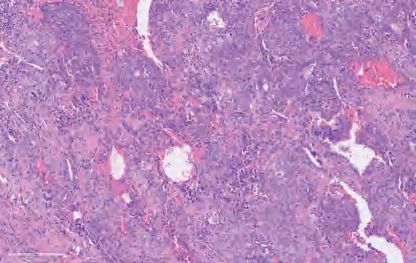

【镜下形态】腺鳞癌由腺癌和SCC两种成分混合组成,在腺癌成分中可以看到任何组织学类型的腺癌,SCC成分可以是角化性或非角化性亚型。如果每种癌成分都分化良好,则诊断腺鳞癌并不困难,不需要通过免疫组织化学来诊断(图2-10)。如果肿瘤具有部分实性腺癌成分或非角化性SCC成分,则诊断更加困难。如果两种肿瘤成分是离散的,则诊断相对容易;如果它们合并混合,则诊断相对困难。腺癌的最佳免疫组织化学标志物是TTF-1,SCC的最佳免疫组织化学标志物是p40。由于10%~20%的肺腺癌TTF-1表达呈阴性,所以有时可能需要做黏蛋白染色来确认TTF-1阴性的实性成分中是否有腺癌分化。如果存在少量腺癌成分,但其比例未达到10%,也应在报告中注明,因为无论腺癌比例如何,肿瘤都可能携带腺癌相关的驱动基因突变。要明确两种肿瘤成分,取材范围至关重要。对于<3 cm的肿瘤,宜对整个肿瘤进行取样;对于较大的肿瘤,每1 cm至少取一个切片。腺鳞癌的诊断需要基于手术切除标本,小活检或细胞学标本检查不能直接作出腺鳞癌的诊断,仅能提出建议。

图2-10 腺鳞癌